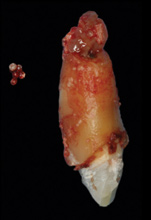

8. Tooth No. 8 with diagnosis of Grade III socket, requiring extraction followed by guided bone regeneration and a rotated pedicle flap to gain hard and soft tissue for future implant placement.

Figure 8

9. Tooth No. 8 with diagnosis of Grade III socket, requiring extraction followed by guided bone regeneration and a rotated pedicle flap to gain hard and soft tissue for future implant placement.

Figure 9

10. Tooth No. 8 with diagnosis of Grade III socket, requiring extraction followed by guided bone regeneration and a rotated pedicle flap to gain hard and soft tissue for future implant placement.

Based on the single extraction socket roadmap developed by El Chaar and colleagues, the socket of tooth No. 8 was diagnosed as Grade III and would require initial treatment that included the extraction of failing tooth No. 8 followed by simultaneous guided bone regeneration and soft-tissue augmentation by means of a rotated palatal pedicle flap (Figure 8 through Figure 11).27,28 The principles of and guidelines for both the ridge augmentation and rotated pedicle flap have been described in the literature and will not be focused on in this case report.27-30 The patient was temporized with a bonded Maryland bridge that was adjusted to avoid creating pressure on the tissue during healing (Figure 12).